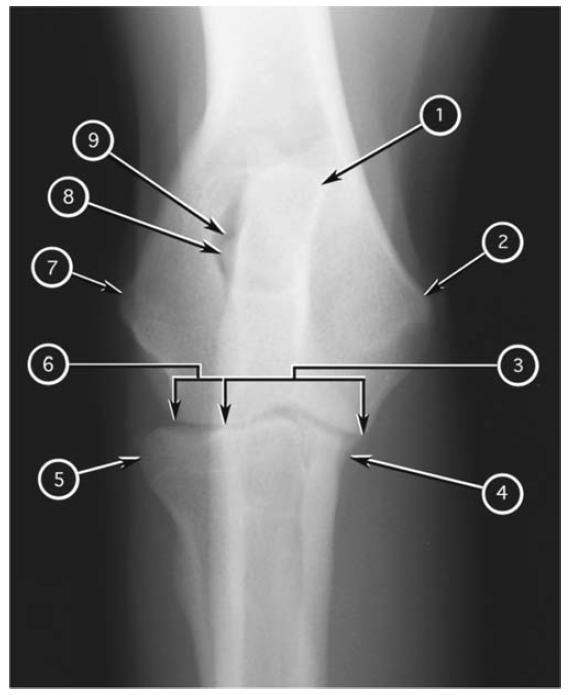

Mediolateral radiograph of canine antebrachium

What number?

- Condyle of humerus

- Lateral epicondyle of humerus

- Medial epicondyle of humerus

- Elbow (cubital) joint

- Tuber olecrani of ulna

- Body of ulna

- Distal metaphysis of ulna

- Distal epiphysis of ulna

- Proximal radioulnar joint

- Head of radius

- Body of radius

- Neck of radius

- Distal metaphysis of radius

- Distal physis of radius

- Distal epiphysis of radius

- Antebrachiocarpal joint

- Accessory carpal bone

- Carpal pad

A

1. Tuber olecrani of ulna

2. Lateral epicondyle of humerus

3. Medial epicondyle of humerus

4. Proximal radioulnar joint

5. Body of ulna

6. Distal metaphysis of ulna

7. Distal epiphysis of ulna

8. Accessory carpal bone

9. Carpal pad

10. Antebrachiocarpal joint

11. Distal epiphysis of radius

12. Distal physis of radius

13. Distal metaphysis of radius

14. Body of radius

15. Neck of radius

16. Head of radius

17. Elbow (cubital) joint

18. Condyle of humerus